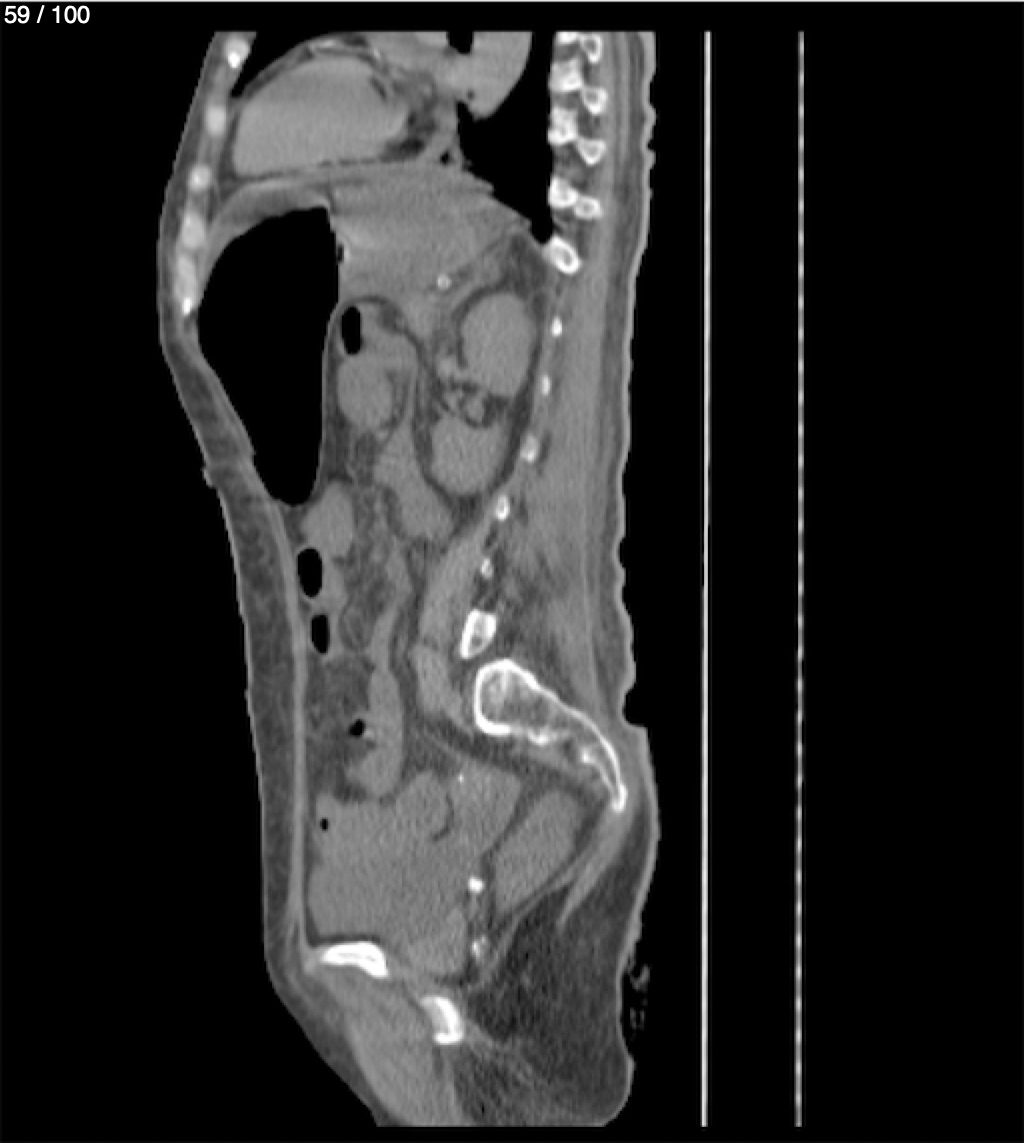

Hilda Geronimo Mendez 60A - T.C Abdomen Simple